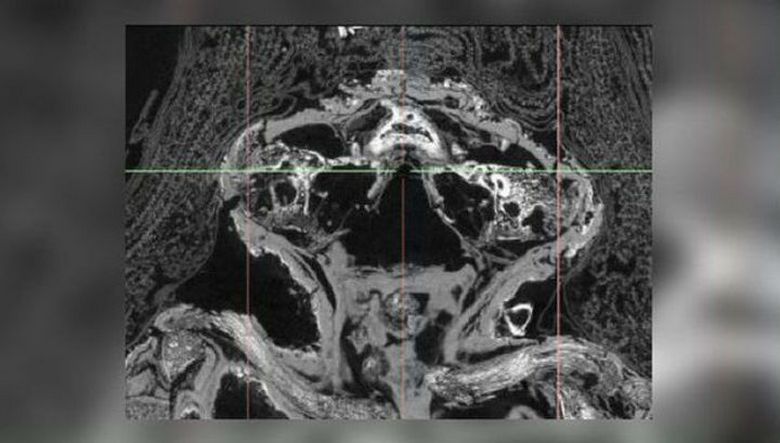

Ja juuri äskettäin “falcon muumio” alistettiin perusteellisesti skannaus (mikro-CT-skannaus antaa tutkijoille mahdollisuuden nähdä, ja tarkoittaa ja tutkia muumion sisäistä sisältöä huolellisesti poistamatta ja rikkomatta sen hautajaismateriaalia) yhdessä muun museon kanssa näyttelyissä. Mikä oli tutkijoiden yllätys, kun he tajusi, että nämä jäännökset eivät kuulu lintuun, mutta kuolleena syntynyt ennenaikainen vauva.

Kävi ilmi, että tämä lapsi kärsi edelleen kohdussa niin harvinainen sairaus kuin enkefali, jossa ne eivät kehitty itse aivot ja kallo, mikä aiheutti keskenmenon. Lapsi oli noin 25 viikkoa vanha, hän oli jo muodostunut vartalo, raajat, jopa varpaat ja käsivarret, mutta kallon yläosa – ei. Lisäksi hän kärsi synnynnäisestä huulilipasta – niin kutsutaan suulakevirtaksi. Toinen asia on yllättävä: mistä syystä tämä on keskenmeno muumautui? Yleensä sellaiset “lapset” muinaisessa Egyptissä (eikä vain siinä) vain haudattu ruukuihin ja vain harvimmat tapaukset tekivät tarkalleen kuten näemme – muumioitunut. Ilmeisesti lasta pidettiin erityisenä ja hänen kuolleena syntynyt – arvokas lähtö kuolleiden maailmaan …